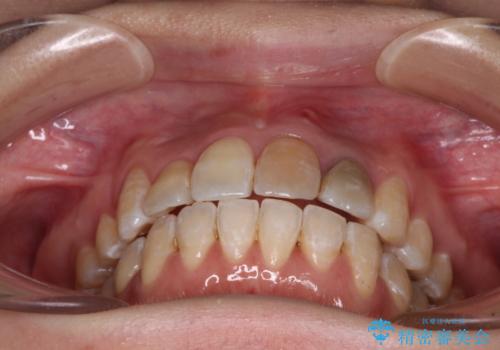

内側に転位していた歯はきれいに歯列に収まり、清掃性が著しく改善しました。

元々神経の失活してしまっている前歯2本は変色が目立つようになってきたため、今後セラミッククラウンによる補綴治療を行う予定です。